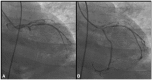

Case summary: We describe a case report of a 74-year-old man with acute chest pain and an electrocardiogram with broad R waves, a 4 mm ST-segment downsloping (excessively discordant) in right precordial leads, RBBB, and ST-segment elevation in posterior leads. There was resolution of ST-segment downsloping in right precordial leads after percutaneous coronary intervention and stenting of the circumflex artery, with disturbance of the repolarization process only attributable to RBBB.